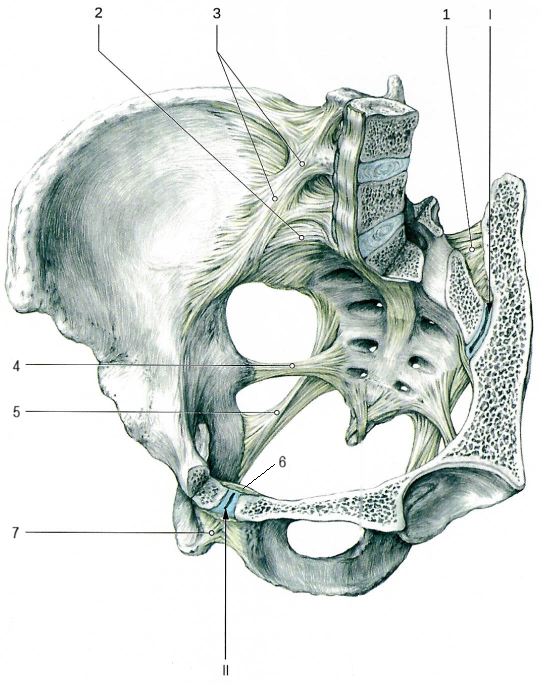

Крестцово-позвздошный сустав по строению простой, по форме плоский, по функции многоосный, однако движения в суставе отвутствуют.

Сустав образован ушковидными поверхностями подвздошной кости и крестца.

Связки, укрепляющие сустав.

Лобковый симфиз[II] соединяет симфизиальные поверхности двух лобковых костей, между которыми расположен волокнисто-хрящевой межлобковый диск.

Лобковый симфиз укреплён следующими связками:

Лобковый симфиз имеет ярко выраженные половые особенности. У женщин это соединение менее высокое и более толстое. Во время родов у женщин в лобковом симфизе возможны небольшие движения.

Помимо суставов и укрепляющих их связок, тазовые кости соединяются с крестцом с помощью двух мощных внекапсульных связок.